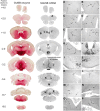

Neurogenetic disorders typically affect cells throughout the brain. Adeno-associated virus (AAV) vector-mediated transfer of a normal cDNA can correct the metabolic defects at the site of injection, but treatment of the entire brain requires widespread delivery of the normal gene and/or protein. Current methods require multiple injections for widespread distribution. However, some AAV vectors can be transported along neuronal pathways associated with the injected region. Thus, targeting widely dispersed systems in the CNS might be a pathway for gene dispersal from a limited number of sites. We tested this hypothesis in the ventral tegmental area (VTA), a region with numerous efferent and afferent projections. A single 1 mul injection resulted in transport of the vector genome to projection sites in distal parts of the brain. When compared with injections into the striatum, the VTA injection resulted in higher enzyme levels in more regions of the brain. The AAV-9 serotype vector was the most widely disseminated, but AAV-Rh.10 and AAV-1 were also transported after VTA injection. The effect on global lesions of a neurogenetic disease was tested in the mouse model of MPS VII (mucopolysaccharidosis VII), a lysosomal storage disorder. Widespread distribution of the vector genome after AAV-9 VTA injection resulted in even further distribution of the enzyme product, by secretion and uptake by surrounding cells, and complete correction of the storage lesions throughout the entire brain. This unprecedented level of correction from a single injection into the developed brain provides a potential strategy to correct a large volume of brain while minimizing the number of injections.